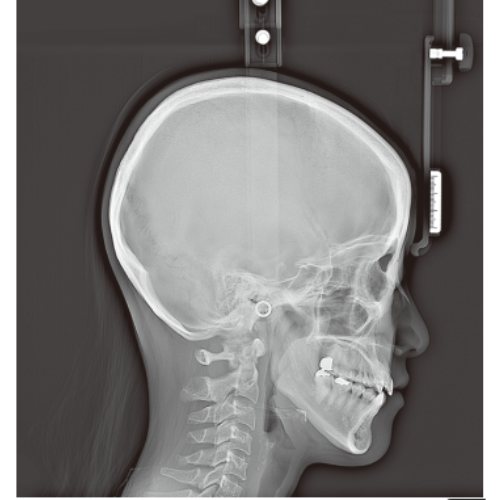

RayScan Alpha Expert Pan + Ceph + CBCT (9x9 FOV) with PC, Software, Installation, Shipping and Warranty

RayScan Alpha Expert Pan + Ceph + CBCT (9x9 FOV) with PC, Software, Installation, Shipping and Warranty

Rayscan Alpha brings another innovative technology with less Recon time and bigger FOV Size. And there are also new features – Fast scan mode, Object scan and Multi FOV.

- Panoramic

- Cephalometric